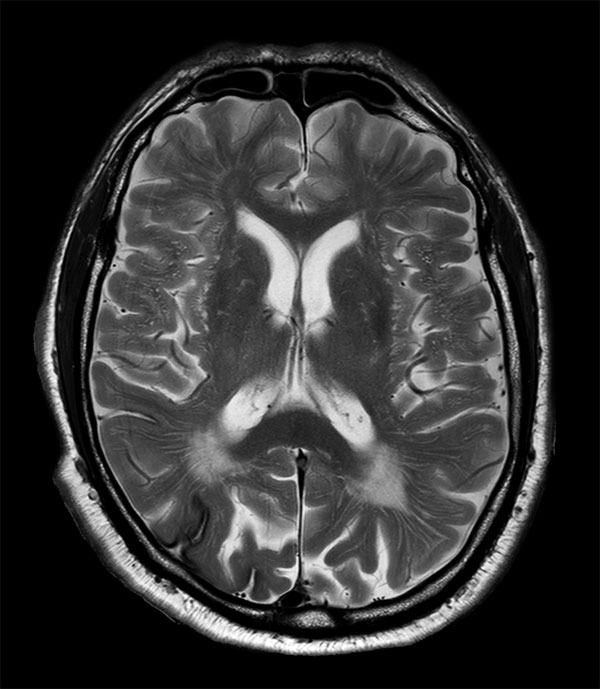

76-year-old male with history of amyloid angiopathy. Sagittal T1-weighted images shows chronic deep white matter ischemic changes. Axial T2-weighted and FLAIR demonstrate chronic ischemic changes and old hemorrhage / hemosiderin staining. Axial Venous BOLD (Susceptibility Weighted Imaging) image show chronic ischemic changes and old hemorrhage / hemosiderin staining. Imaging appears consistent with amyloid angiopathy, no other intracranial lesions are found.

Axial T2w TSE